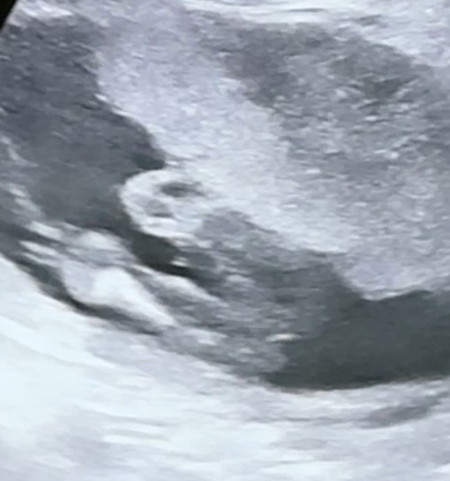

กำหนด10พฤษภาคม 64 แต่ออกวันที่ 30 เมษายน 64 น้องเป็นผู้ชาย น.น3180กรัม ค่ะ อาการคือ #หายใจเรว #แขนข้างขวาโดยหนีบเนื่องจากเชิงกรานแม่แคบทำให้เราไม่สามารถขยับแขนได้ แล้วเด็กใหญ่ ก่อนคลอด 29 เมษายน หมออัลตร้าซาวด์ น.น2700กรัม หมอเลยปล่อยให้คลอดเองธรรมชาติ ตอนนี้น้องอยู่ห้องอภิบาลเด็กแรกเกิด เป็นกำลังใจให้น้องด้วยนะคะ